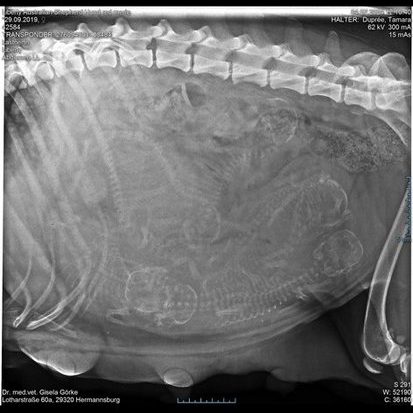

Röntgen

Wir setzen Röntgenuntersuchungen für unsere Hündinnen ein, um ihre Gesundheit auf die bestmögliche Weise zu garantieren. Diese entscheidenden Diagnosetools sind unerlässlich, um mögliche Hüft- und Ellenbogendysplasien sowie Anomalien der Wirbelsäule frühzeitig zu erkennen. Nur so können wir sicherstellen, dass unsere geliebten Vierbeiner ein langes, glückliches Leben führen. Dieses verantwortungsvolle Vorgehen schützt nicht nur die Gesundheit unserer Hündinnen, sondern gibt auch uns, ihren Menschen, die Gewissheit, dass wir alles tun, um ihnen die bestmögliche Lebensqualität zu bieten.